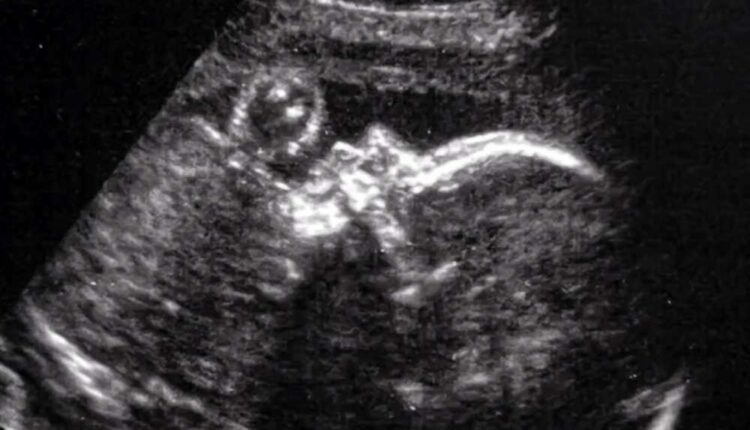

Η δυσπλασία συχνά αποκαλύπτεται κατά τη διάρκεια προγεννητικού υπερηχογραφήματος και διαγιγνώσκεται με μαγνητική τομογραφία κατά το τέλος του δεύτερου ή τρίτου τριμήνου της εγκυμοσύνης.

Η Ντένβερ Κόουλμαν γεννήθηκε δύο μέρες μετά την επέμβαση. Φωτ.: CNN

Σύμφωνα με τη μελέτη, το έμβρυο, στο οποίο έγινε η πρωτοποριακή επέμβαση, είναι η Ντένβερ Κόουλμαν, η οποία γεννήθηκε δύο ημέρες μετά την επέμβαση, στις 17 Μαρτίου, κάτι λιγότερο από 1.900 γραμμάρια.